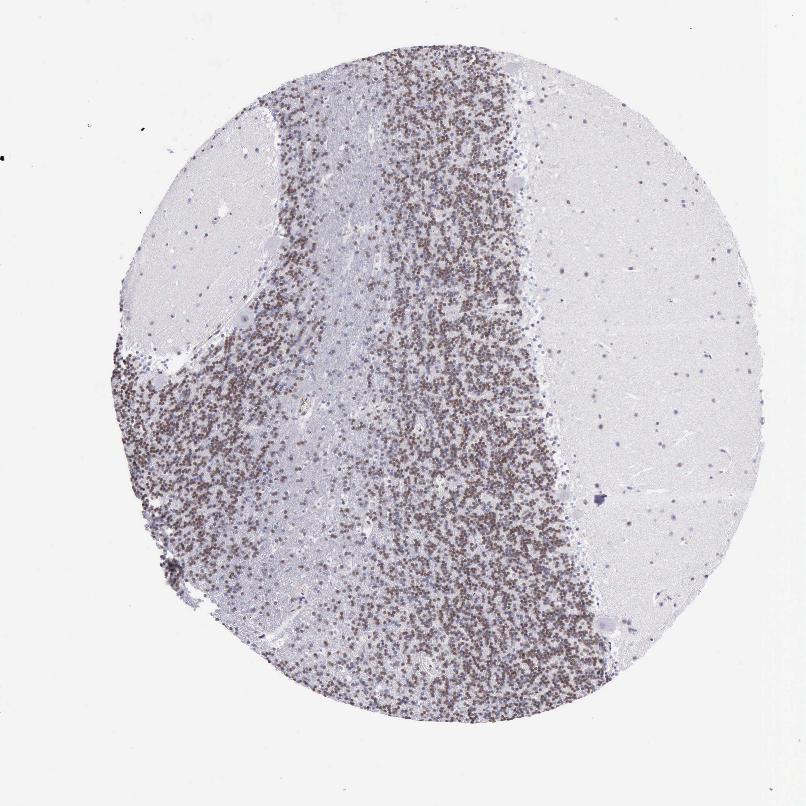

CEREBELLUM - Antibody stainingi

Antibody staining in the annotated cell types in the current human tissue is reported as not detected, low, medium, or high, based on conventional immunohistochemistry profiling in selected tissues. This score is based on the combination of the staining intensity and fraction of stained cells.

Each image is clickable and will lead to virtual microscopy that enables deeper exploration of all samples and also displays staining intensity scores, fraction scores and subcellular localization as well as patient and tissue information for each sample.

Antibody HPA003128Antibody HPA004112Antibody CAB000146

Purkinje cells MediumHigh-

Cells in granular layer MediumLow-

Cells in molecular layer MediumMedium-